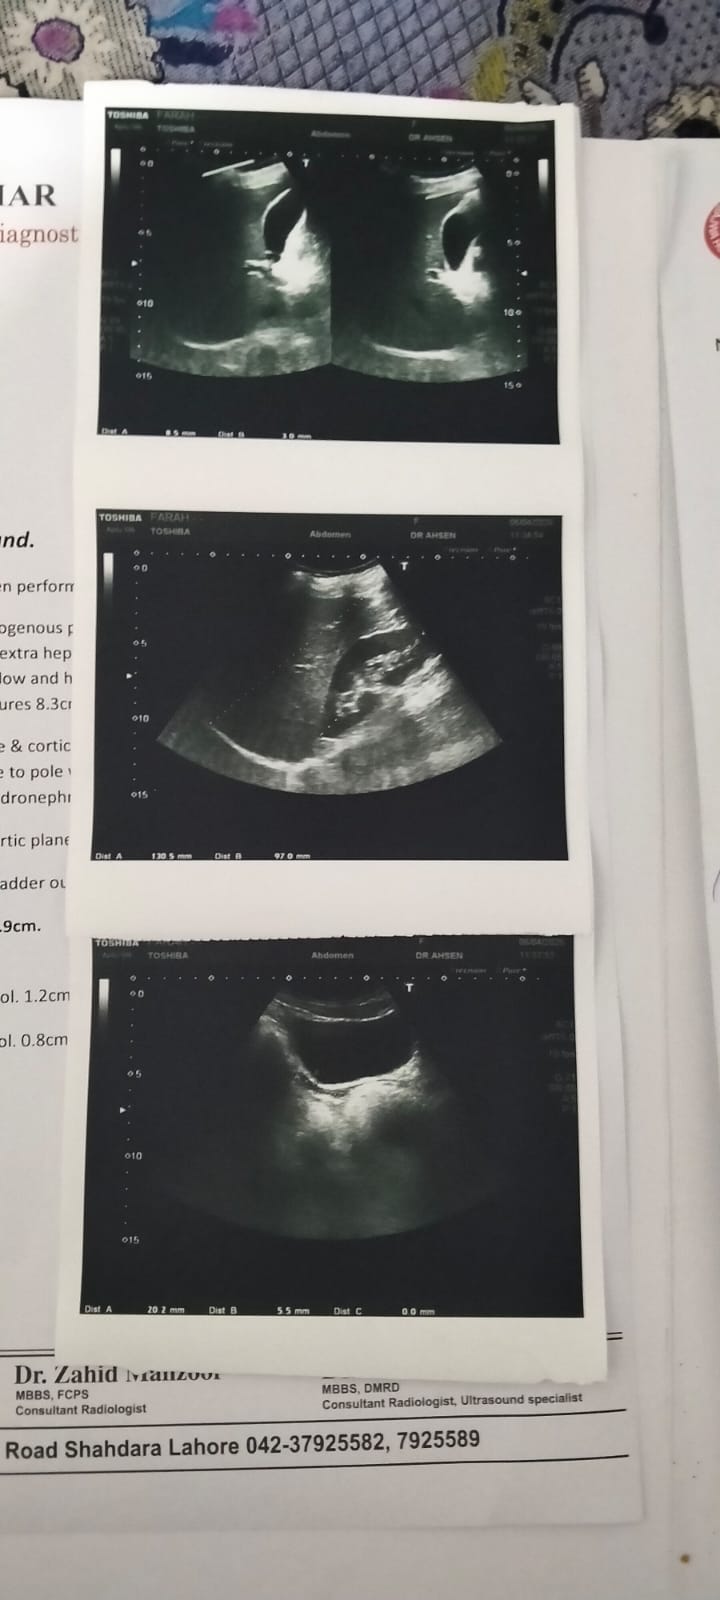

Asking for Sister, Female, 25 years old, Shadhra lahore

Chota uterus ha or kabhi b period nhi aay is time Umar 25 ha to Kya treatment possible ha is ka

Attach Photo here: